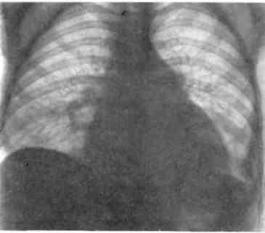

Вовлечение лѐгких наблюдается у 70% больных ССД и по частоте уступает только поражению пищевода. Основными клинико-морфологиче- скими видами поражения лѐгких при ССД являются интерстициальное заболевание лѐгких (фиброз лѐгких) (рис. 5-6) и лѐгочная гипертензия.

Рис.5-6. Двухсторонний диффузный пневмосклероз (рентгенограмма и компьютерная томограмма).